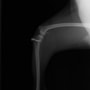

■ 症例24 キャバリア 7か月

左右膝蓋骨内方脱臼(左:グレードⅣ 右:グレードⅢ)

以前から左右後肢の跛行が認められ、整形外科学的検査・レントゲン検査により左右の膝蓋骨脱臼が認められた。症状が重度である左膝の膝蓋骨脱臼整復術を行った。外科手技は縫工筋及び内側広筋の解放、脛骨粗面の外側転位、滑車ブロック形造溝術、内外側関節方の縫縮を実施した。術後一か月時点で、左の膝蓋骨は安定しており経過は良好である。

本症例は成長期における重度の膝蓋骨脱臼であり、術後の再発の可能性もあるため、経過をしっかりと観察していく必要がある。また、今回手術を実施していない右膝に関しても経過を観察し、手術を検討していくこととする。